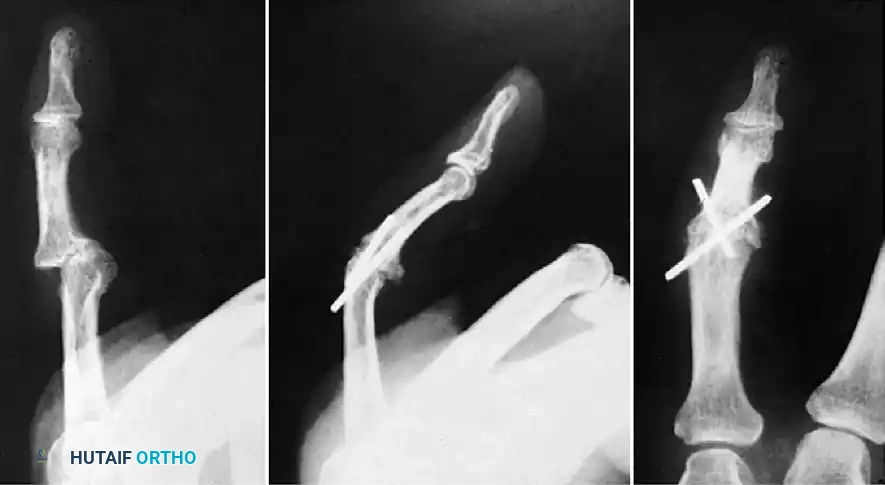

FIGURE 67-62 Radiographs of interphalangeal dislocation in a child. The injury had gone undiagnosed for 1 month because the deformity appeared slight externally. After open reduction, flexion of 30 degrees was eventually possible.

Surgical Warning: Neglected dislocations lead to rapid contracture of the collateral ligaments and volar plate, accompanied by progressive articular cartilage necrosis. Open reduction of a neglected dislocation often yields suboptimal range of motion, emphasizing the critical need for immediate, accurate radiographic diagnosis.